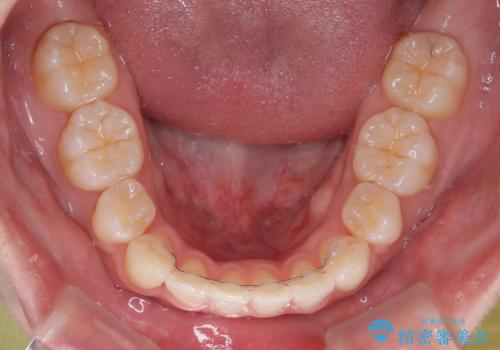

結婚式で途中装置を外した時期がありましたが、2年で治療を終えることができました。